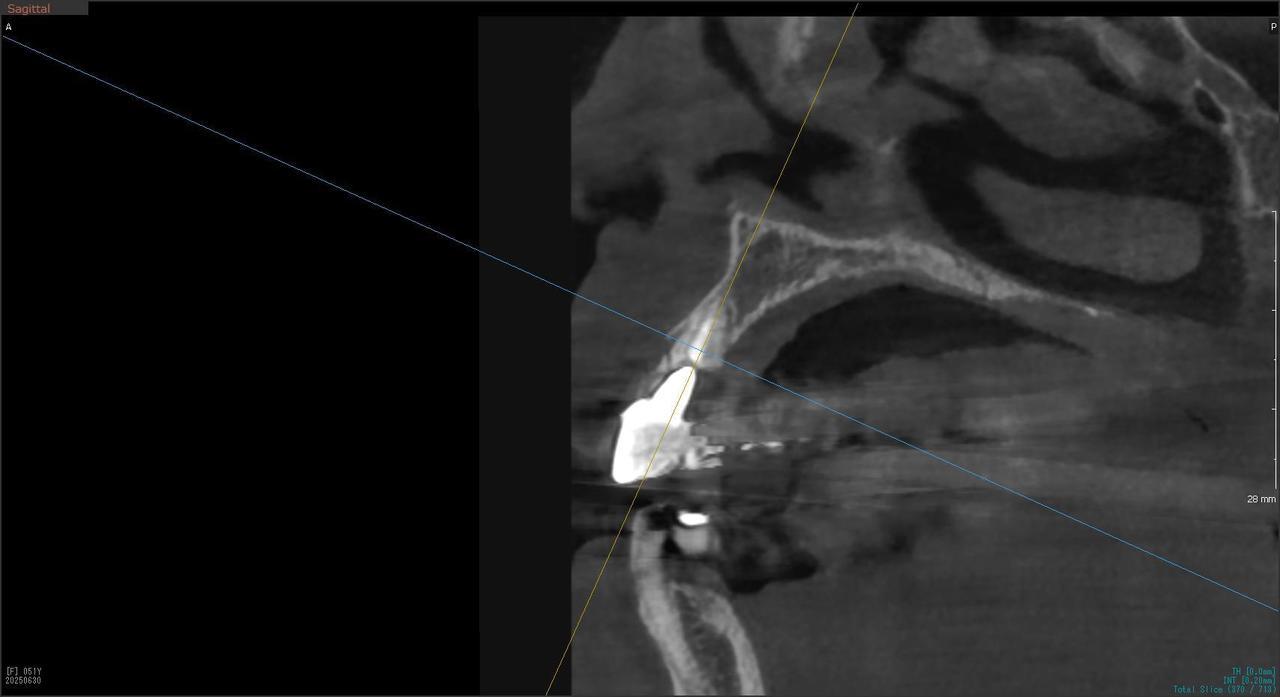

4.右上5が折れたために、インプラント抜歯即時埋入をおこなったインプラント治療のケース。

Before

枚方市のインプラントの症例

After

T・T 様 女性 40代

症状としては、 右上5番の歯が折れてしまった。保存することは不可能な状態であった

治療法としては、患者様は、歯が折れたことを主訴に来院。インプラント治療を希望したため、抜歯した当日に、インプラント埋入をおこなって、骨欠損部には人工骨を補填した。1か月半後にインプラントが骨と結合していることを確認できたため、光学印象を行い、2か月後に、最終補綴物として、アバットメントとジルコニアクラウンの装着を行いました。

治療結果としては、抜歯したと同時にインプラントを埋入することで、抜歯した穴が自然に治る過程で、インプラントの骨結合と組織の治癒が同時に行われるために、2か月という治療期間で治療を終了することができたことと、機能面・審美面でも回復を行うができた。

治療の期間・回数:約2か月、インプラント抜歯即時埋入から最終補綴物装着まで4回

治療の価格:352,000円(税込)

治療費の内訳:インプラント基本料(フィックスチャー及び手術費用、投薬費用、レントゲン費用、インプラント上部費用(アバットメントおよびジルコニアクラウンの費用用)330000円(税込み)。オプション、抜歯即時埋入加算(人工骨費用を含む) 22000円(税込み)

治療のリスクや副作用:手術後に、痛みや腫れ、出血、合併症などを引き起こす可能性があります。噛む感覚がご自身の歯と異なる場合があります。見た目がご自身の歯と異なる場合があります。手術後にメインテナンスを継続しないと、インプラントが抜け落ちる可能性があります。